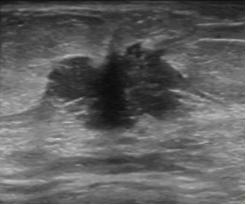

3.乳腺结节的边缘。

分为:光整和不光整(模糊、成角、微小分叶、毛刺等)。边缘光整是指:结节的边缘与周围组织界限清晰,往往是良性结节的特征。结节边缘不光整往往是乳腺癌的征象,指的是:模糊(结节的部分边缘无清晰的边界)、微小分叶(结节边缘出现锯齿状结构)、成角(结节边缘部分或全部形成锋利的角度,通常为锐角)、毛刺(从结节的边缘放射状的锐利细线)。

乳腺恶性肿瘤彩超表现,乳腺结节良性恶性彩超对照图

结节边缘为微小分叶,术后病理为恶性